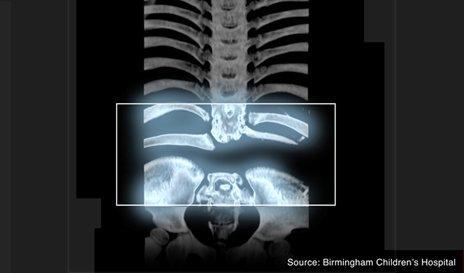

Рози Дэвис охин эхээс мэндлэхдээ л нуруунд нь 10 см хэрийн зайтай яс ор байхгүй төржээ. Одоо таван настай охины дотор эрхтэн үүнээс болоод байр байраа алдаж, ажиллагаагүй болоход хүрсэн тул нурууны ясыг нь хөлийнхөөр нь орлуулж нөхөх мэс заслыг хийсэн байна. Охины нурууны таван яс байхгүйгээс гадна хөлийнх нь доод хэсэг бараг мэдрэлгүй шахам байсан учир амь насыг нь аварч, дотор эрхтнүүдийнх нь хэвийн үйл ажиллагааг хангахын тулд тэр хэсгийн ясыг авч, нурууны хоосон хэсэгт тавьж нөхсөн байна.

Их Британийн Бирмингамын хүүхдийн эмнэлэгт болсон энэ мэс засал 13 цаг үргэлжилжээ. Нэгэнт түүнд амин чухал хэрэгцээтэй байсан нурууны ясыг бий болгож чадсан учраас охин одоо бүрэн эдгэрсэн цагтаа хиймэл хөл хийгээд, хөл дээрээ босч, явж чадна хэмээн эцэг эх нь сэтгэл өөдрөг байна. Энэ бяцхан охинд хийсэн шиг мэс заслыг өмнө Европт хийж байгаагүй бөгөөд 10 жилийн өмнө Шинэ Зеландад төстэй мэс засал хийж байжээ. Тийм ч учраас мэс заслыг хийсэн эмч нар эмчилгээний үр дүндээ тун сэтгэл хангалуун байгаа гэнэ.